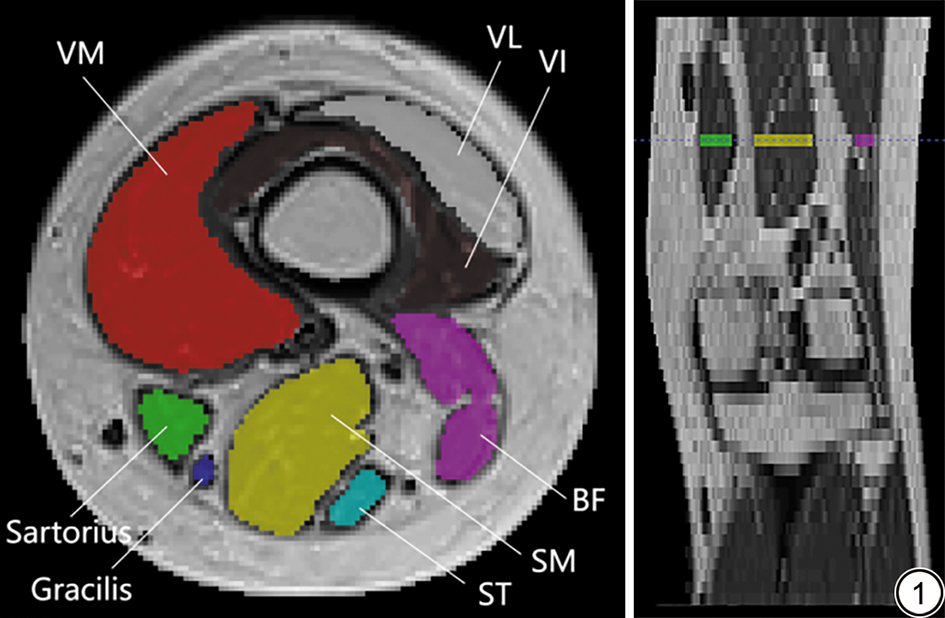

由2名从事骨骼肌肉放射影像诊断3年以上的放射科医师,采用盲法分别对肌肉进行T1、T2及PD值测量,并对测得的数据进行一致性检验。使用ITK-SNAP软件(Version 4.2.0,http://www.itksnap.org/)在集成序列生成的T1WI冠状位重建图上,选取胫骨平台上方22%股骨长度的T1WI横轴位层面(图1),在此层面手动勾画股内侧肌、缝匠肌、股薄肌、半膜肌、半腱肌、股二头肌、股外侧肌、股中间肌的感兴趣区(region of interest, ROI),匹配T1Map、T2Map、PDMap得到相应区域肌肉的T1、T2及PD值。为了减少数据的测量误差,在勾画的过程中避开过拟合像素点,同时尽量避开大血管及肌间脂肪,以减少测量误差。

图1  肌肉分割示意图,层面选择。VM:股内侧肌;VL:股外侧肌;VI:股中间肌;Sartorius:缝匠肌;Gracilis:股薄肌;ST:半腱肌;SM:半膜肌;BF:股二头肌。

Fig. 1  Schematic diagram of muscle segmentation, slice selection. VM: vastus medialis; VL: vastus lateralis; VI: vastus intermedius; ST: semitendinosus; SM: semimembranosus; BF: biceps femoris.